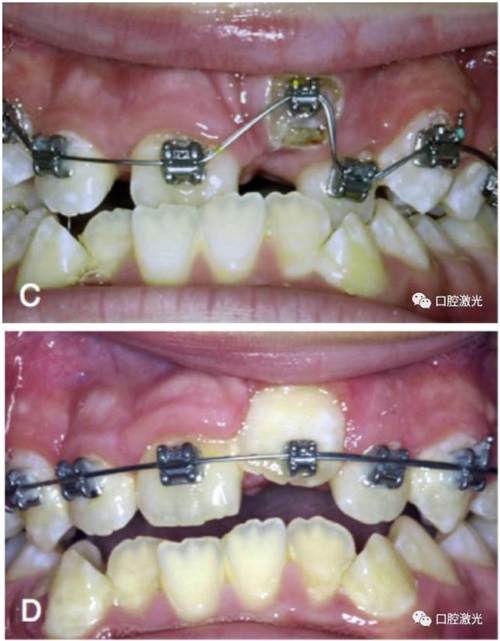

有時,會遇到一些口腔衛(wèi)生問題比較嚴重的患者,從而導致牙齦發(fā)炎而腫大。通過改善口腔衛(wèi)生環(huán)境,炎癥可以得到緩解,但增生的牙齦不一定都可以完全恢復。下圖的患者就存在口腔牙齦肥厚問題,同時左上部犬牙存在部分萌出的問題,右上部犬牙存在未萌出問題,這些問題都妨礙了托槽的粘接。因此,實施了全口腔的牙齦整形手術(shù)。去除了多余的牙齦組織,增加了犬牙的暴露面積,從而使托槽的粘接更為便利,同時也提升了患者保持口腔衛(wèi)生的狀況。

治療前

激光牙齦整形后即刻

激光治療當天粘接托槽

6周后效果